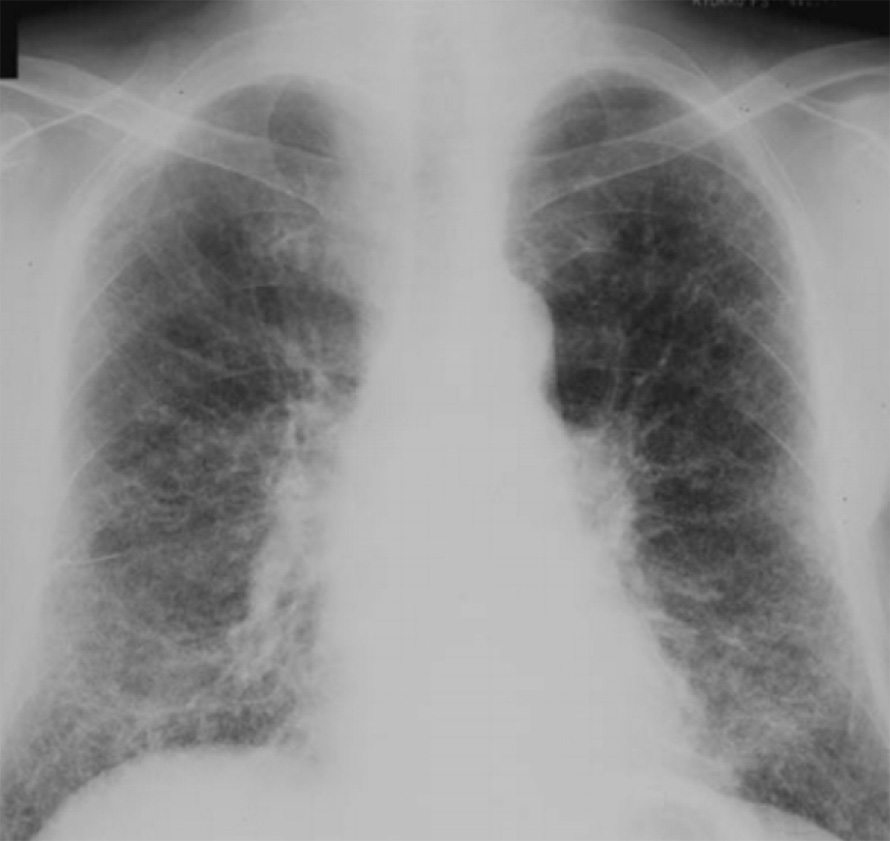

Рисунок 2. Силикоз I-II стадии. В обоих легких определяются многочисленные мелкие узелки, размером 2-3 мм. Изменения преобладают в средних отделах легочных полей